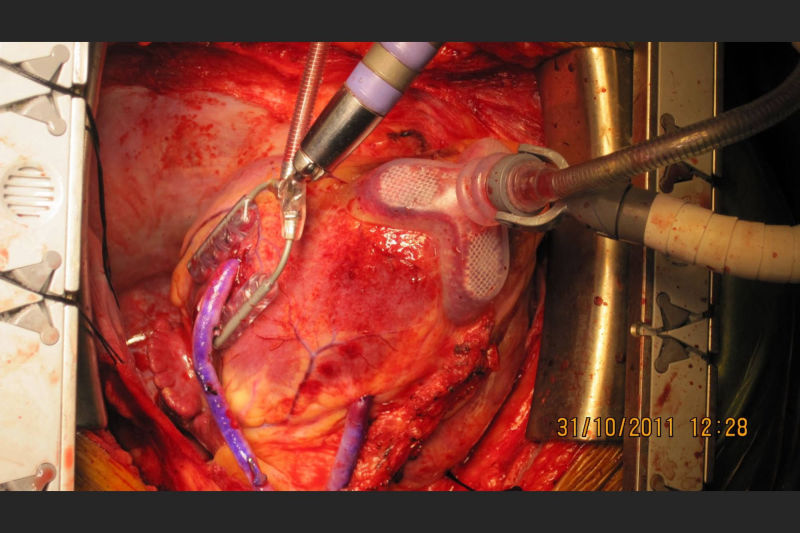

Led Malabar's first successful heart transplantation done at Metromed International Cardiac Centre on a 54 year old patient with end stage heart disease. Donor heart was harvested from a 28 year old gunshot victim in Kannur and brought to MICC through a green corridor. The transplanted patient is healthy and on minimal medication. For end stage cardiac disease, heart transplantation is the gold standard. Post transplant, they have a near normal life.